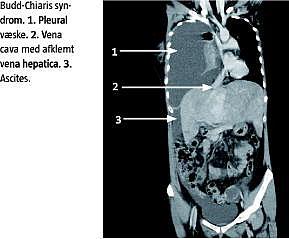

Ved indlæggelsen blev der konstateret »hvidt« højre lungefelt, og der blev udtømt højresidig pleuraansamling af transsudattype. Efterfølgende var der recidiverende dannelse af pleuraansamlinger på op til 5 l pr. døgn. I forløbet blev patienten cerebralt påvirket. En computertomografi (CT) og en magnetisk resonans (MR)-skanning af hjernen viste ingen abnormiteter. CT og MR-skanning af thorax og abdomen viste meget beskedne mængder af ascites i det lille bækken og afklemning af levervener, hvilket var foreneligt med Budd-Chiaris syndrom. Afklemningen af levervenerne og hepatomegalien blev klinisk fejlagtigt tolket som et forbigående og sekundært fænomen, som man antog skyldtes trykdannelse fra de massive pleuraansamlinger.

På grund af fortsat uafklaret sygdomsbillede, yderligere forværring af patientens almentilstand og for at udelukke intraabdominal karcinomatose blev der foretaget diagnostisk laparoskopi, der viste moderat endometriose. Ved en fornyet trefaset CT sås vv. hepaticae ikke, og der kunne konstateres nedsat levergennemblødning, der dog var bevaret ved lobus caudatus. En leverbiopsi, der var blevet taget ved laparoskopien, viste forandringer, som var forenelige med Budd-Chiaris syndrom. Patienten blev overflyttet til Rigshospitalet til anlæggelse af transjugulær intrahepatisk portosystemisk shunt [3]. Videre udredning viste positivt resultat for JAK2 V617F -mutationen, som er karakteristisk for myeloproliferativ sygdom.